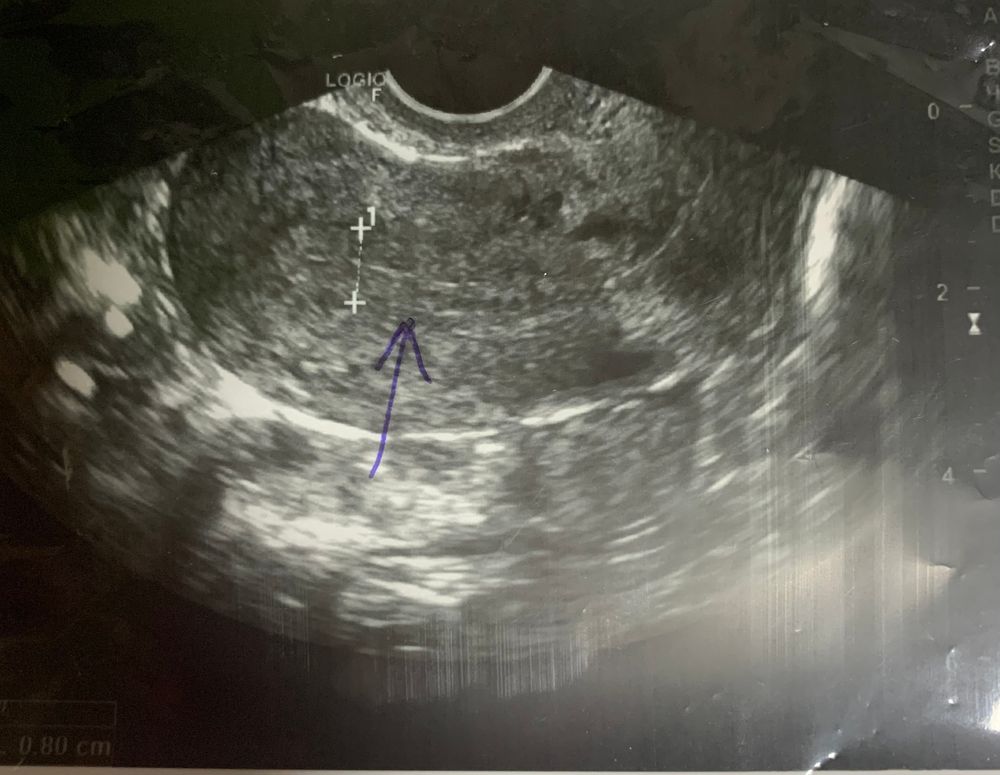

Мама девочки (3 года) Барселона

А на какой день задержки будет видно плодное яйцо 🫣

Я вижу просто матку) сдайте хгч